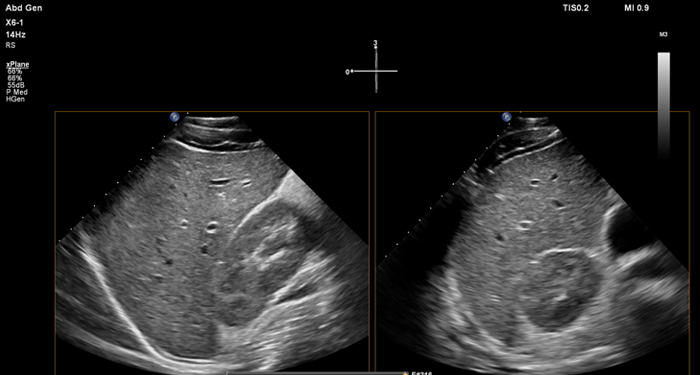

At the touch of a button, the new MaxVue high-definition display brings extraordinary visualisation of anatomy with 1,179,648 additional image pixels compared to a standard 4:3 display format mode. MaxVue enhances ultrasound viewing during interventional procedures and provides 38% more viewing area to optimise the display of dual, side/side, biplane, and scrolling imaging modes.

MaxVue offers a 38% greater viewing area.